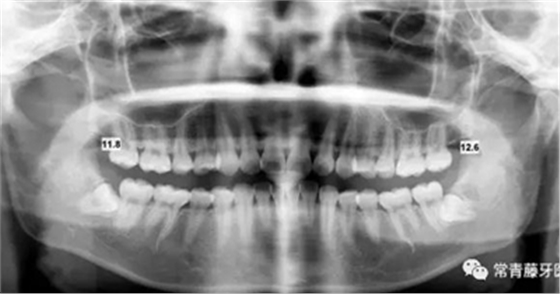

影像學(xué)檢查

曲斷顯示38、48阻生;雙側(cè)TMJ髁突頭略不對(duì)稱(chēng)。

頭影測(cè)量顯示上下頜骨發(fā)育不足,且呈現(xiàn)骨性Ⅱ類(lèi)。

曲斷可見(jiàn)牙根基本平行。